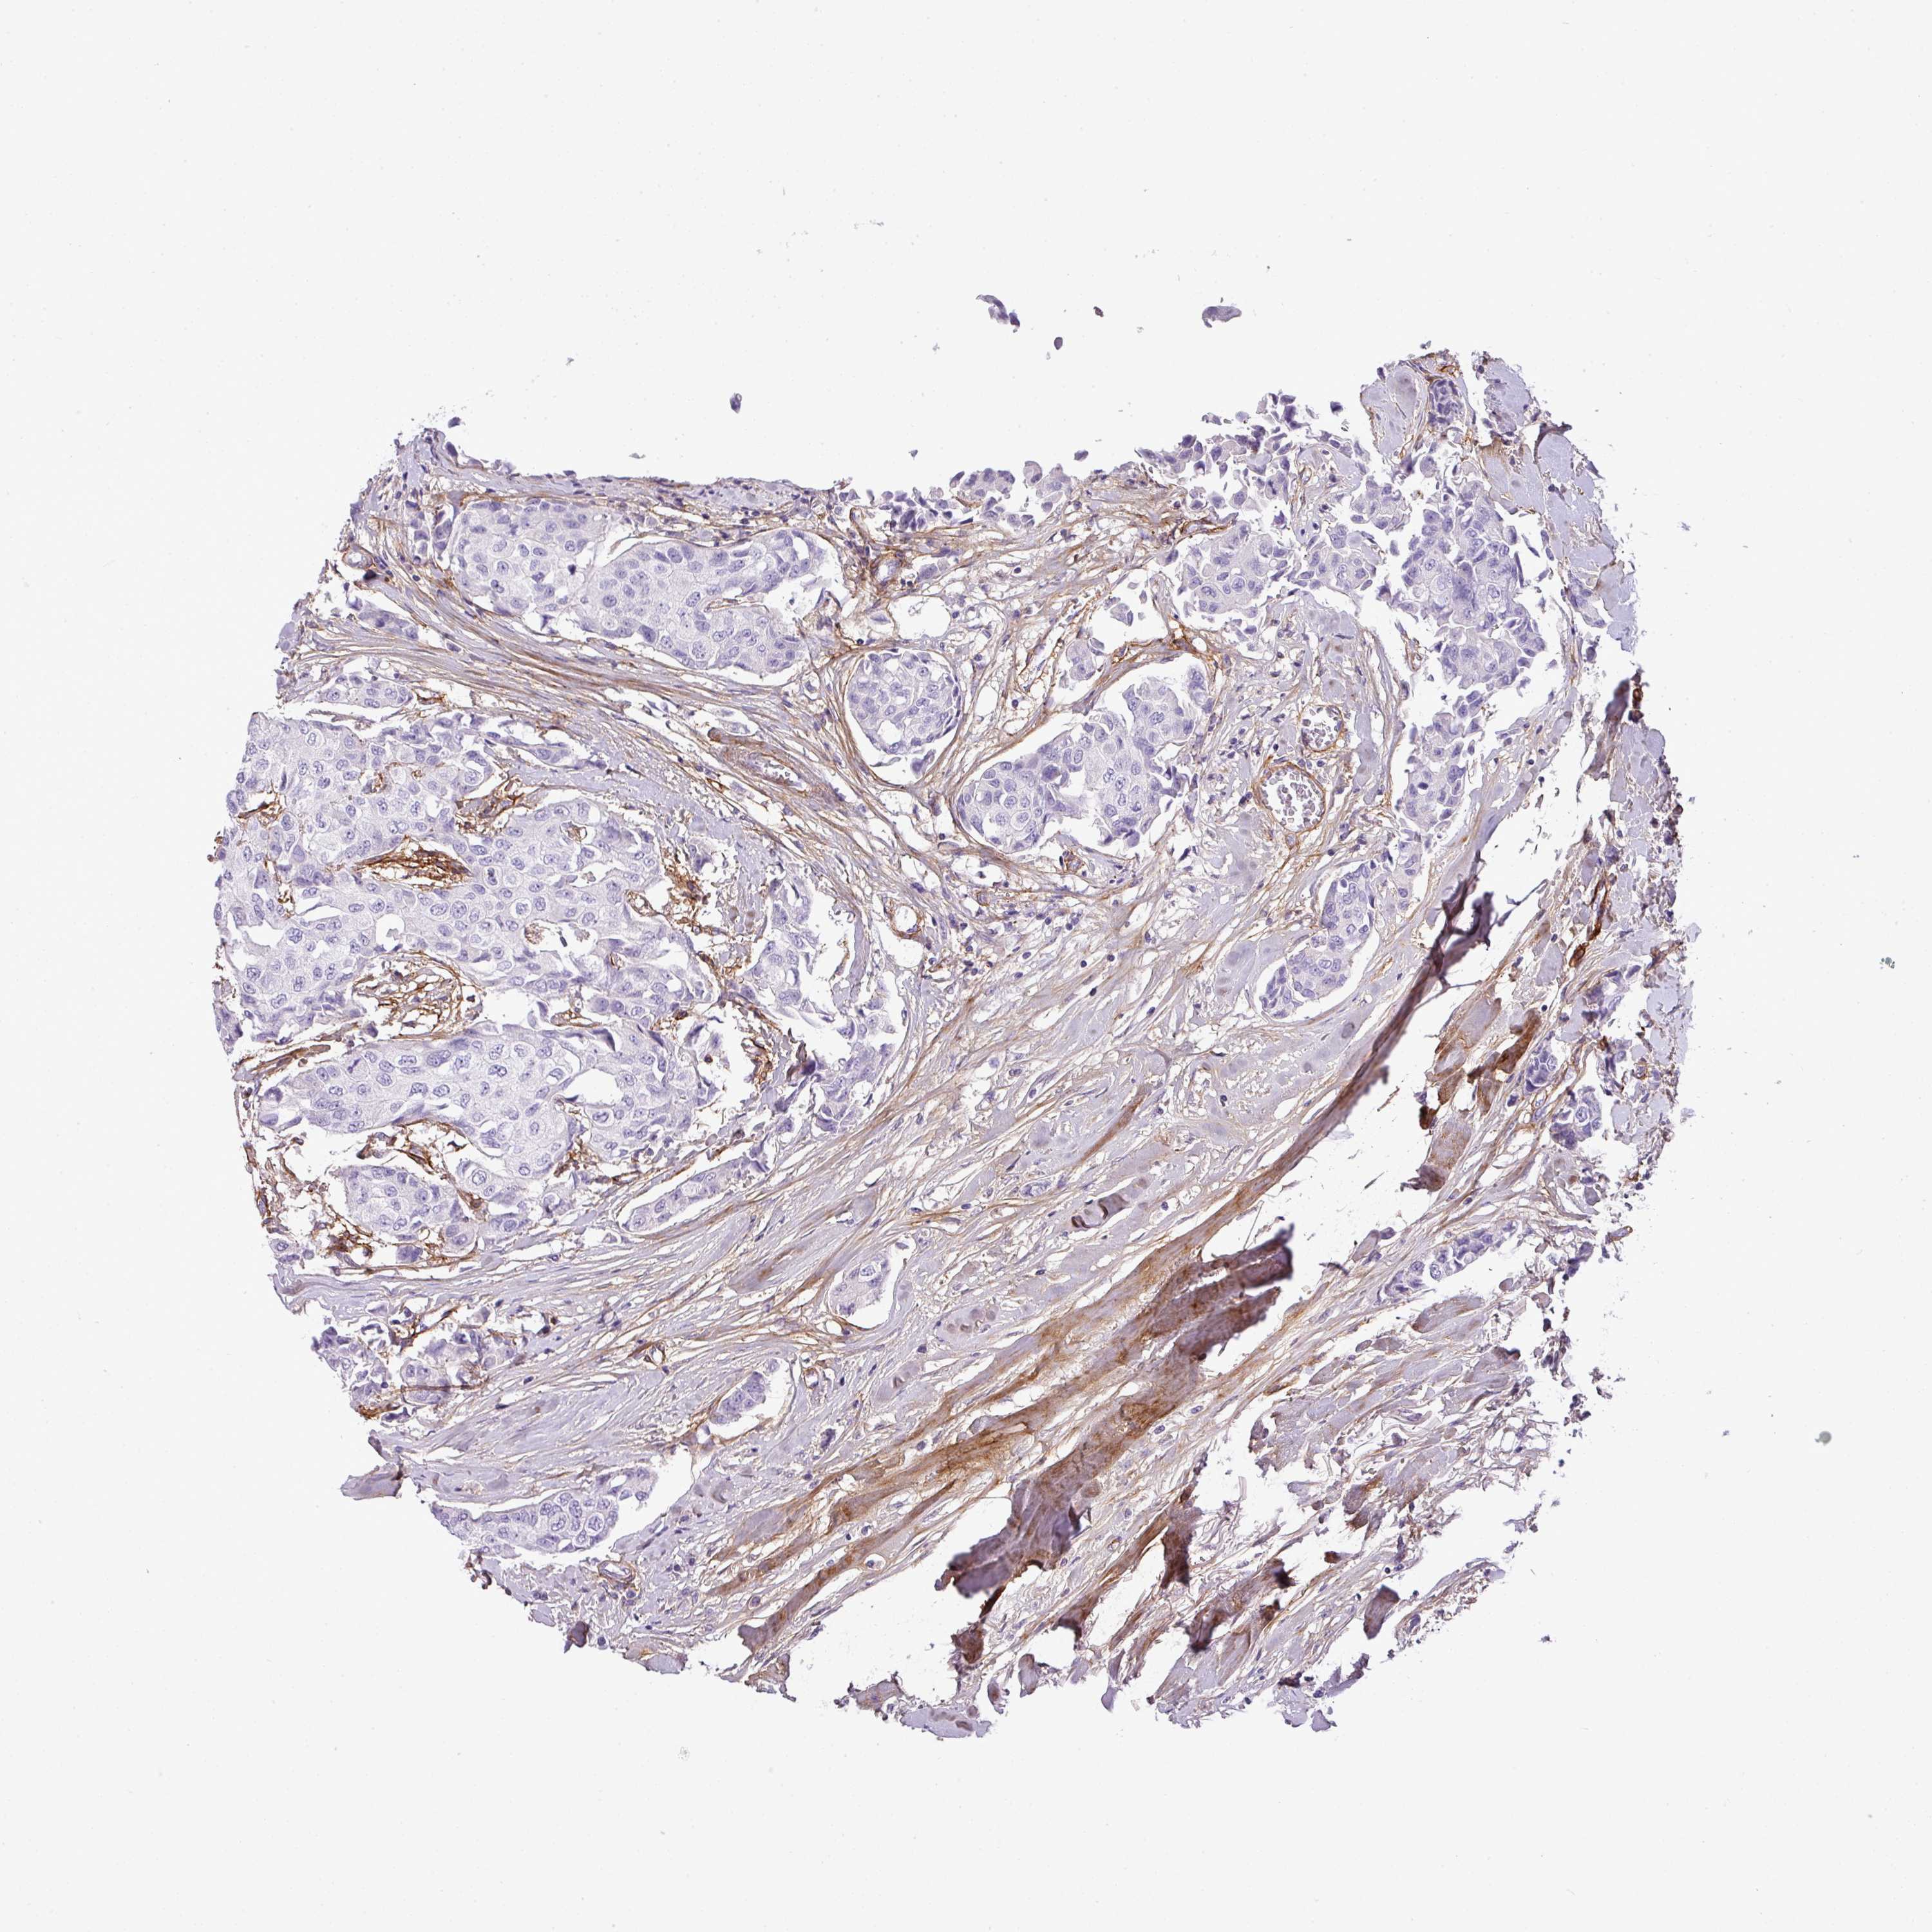

BRCA TCGA BRCA VALIDATION PROTEIN EXPRESSION

ANTIBODIES

AND

VALIDATION